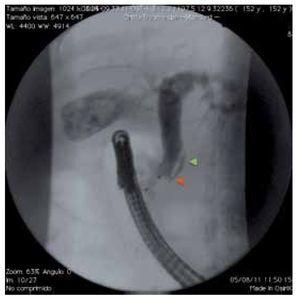

¿ Figura 5. Colangiografía que muestra conducto cístico de implantación baja con espiral. En la imagen se observa un conducto cístico con implantación en el tercio distal del colédoco (punta de flecha roja) y cuya trayectoria describe una curva anterior o posterior (punta de flecha verde) al colédoco antes de su implantación en la cara medial del colédoco.